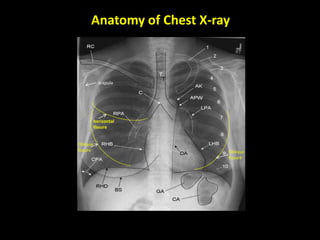

Anatomy of Chest X-ray

scapula

Oblique

fissure

horizontal

Upper lobe

Lower lobe

Left LUNG

Right Lung

Lower

lobe

Middle

2 fissures (oblique and

horizontal).

3 lobes (upper,

middle, lower)

10 segments

1 fissure (oblique)

2 lobes (upper and

lower)

8 segments

Lingula